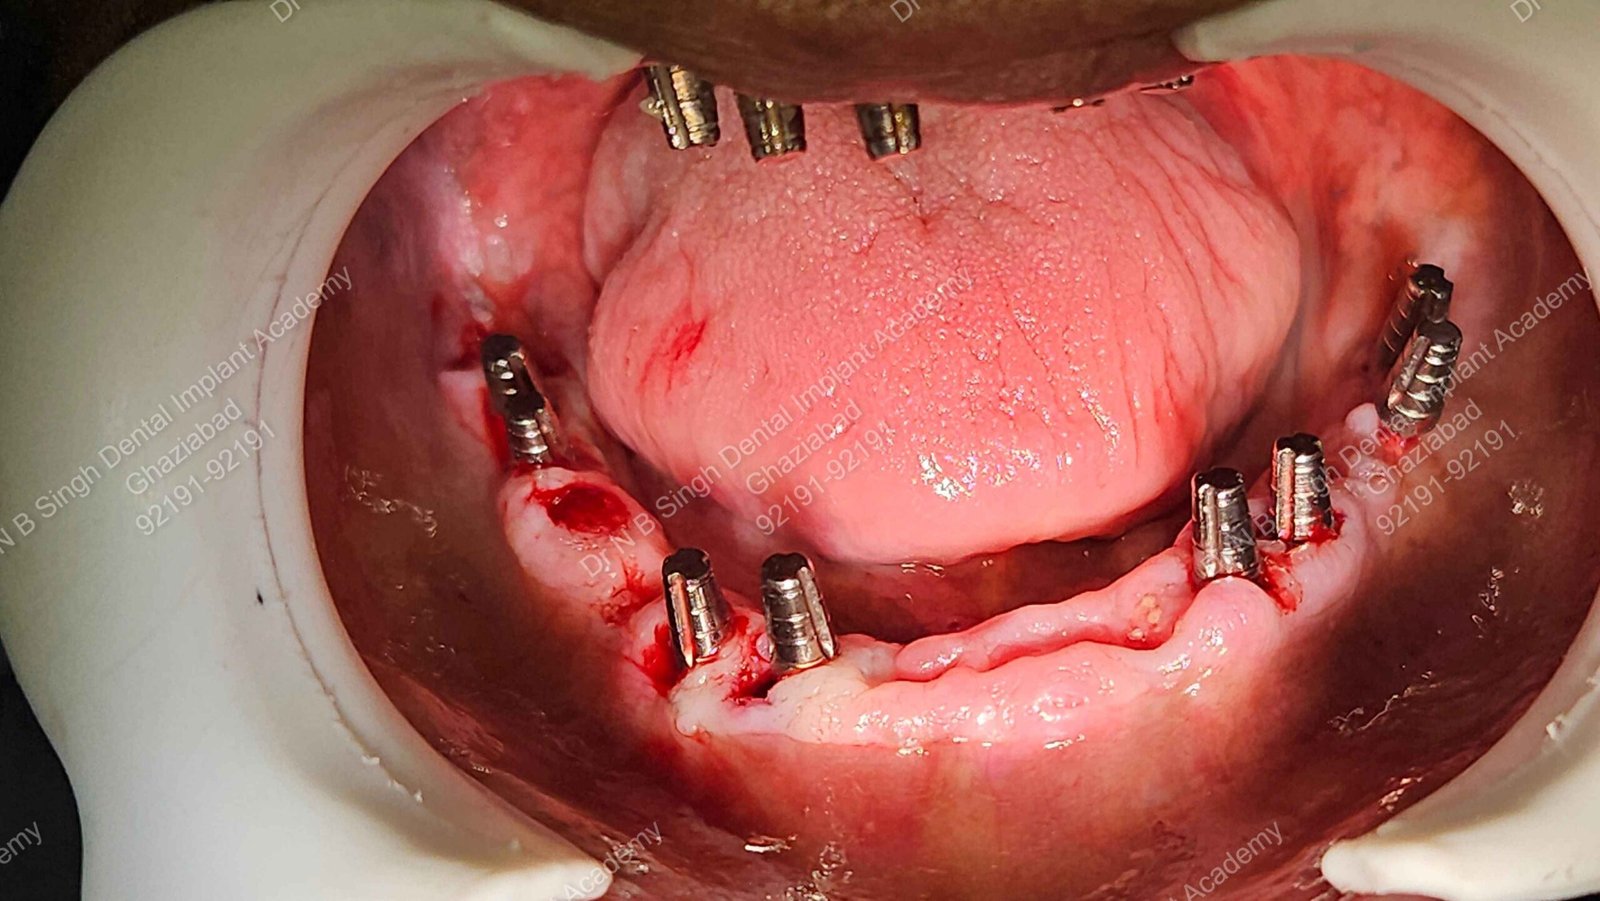

C1005 zygomatic basal implant full mouth – Ali Hasan 4

Dr. N.B. Singh